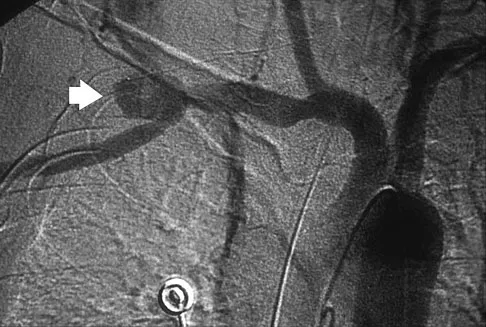

A previously healthy 65-year-old woman has a closed fracture of the right clavicle after falling down the basement stairs. Examination reveals good capillary refill in the digits of her right hand. Radial and ulnar pulses are 1+ at the right wrist compared with 2+ on the opposite side. In the arteriogram shown in Figure 36, the arrow is pointing at which of the following arteries?